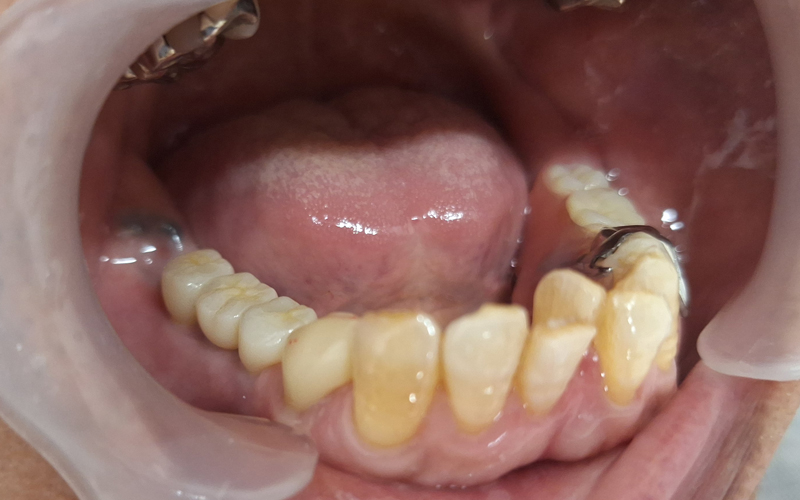

入れ歯が合わない方へのインプラント症例

治療後

主訴

右下の入れ歯が合わない。

治療期間・回数

3ヶ月

治療方法

右下インプラントブリッジ2本(3歯分)※追加処置なし

費用

773,300円(税込み)

デメリット・注意点

自費診療のため費用がかかる。定期メンテナンスが必要。

備考

入れ歯で苦労されてきた方でした。左側の義歯新製後何度か調整致しましたが、現在経過良好です。